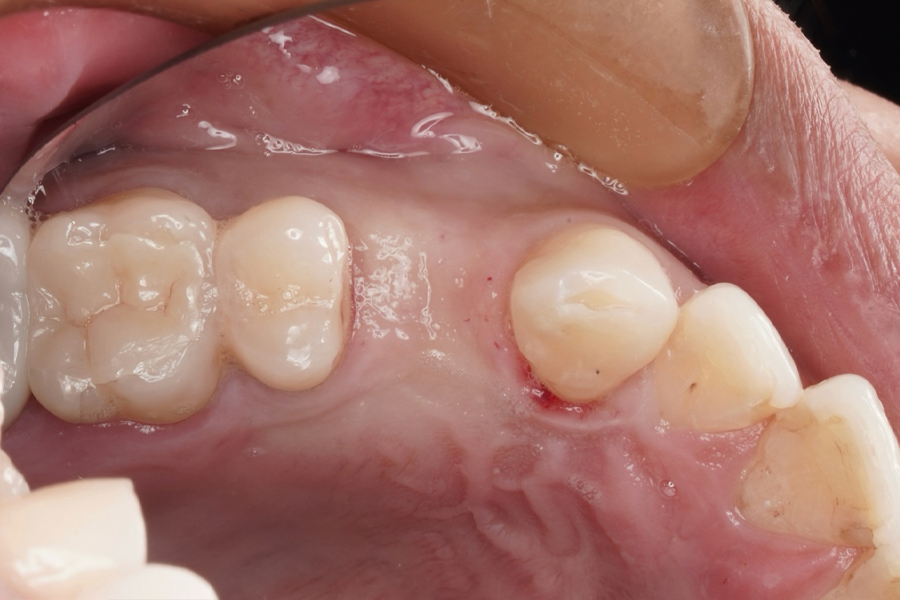

治療前(Before)

歯槽堤温存術前

⚫︎部位:右上第一小臼歯(4番)

| 主訴 | 咬合時の違和感と匂いがする。 |